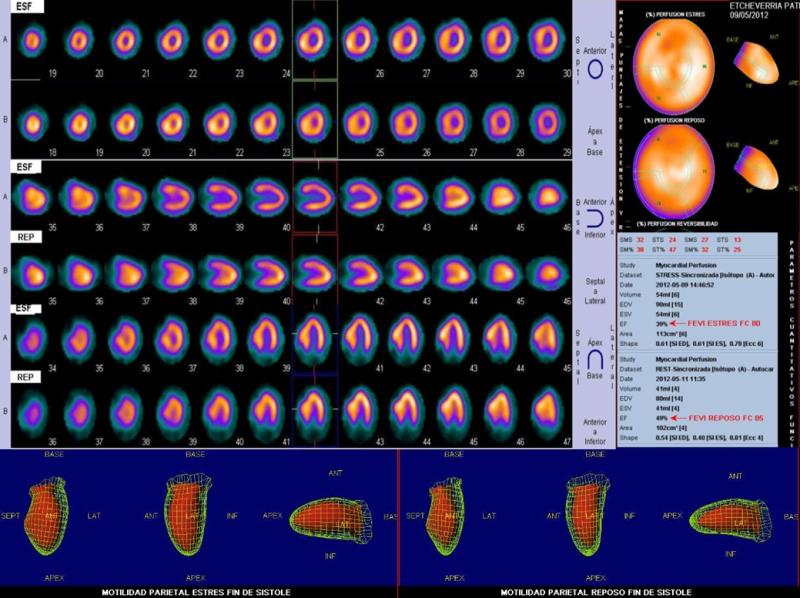

Con los signos y síntomas de la prueba ergométrica y las imágenes obtenidas en el SPM, se plantea el diagnóstico de miocardiopatía hipertrófica con severa obstrucción dinámica del tracto de salida. Se indica tratamiento con beta bloqueantes, comenzándose con bajas dosis por cifras de PA basal de 110/60 mmHg y se suspende la actividad física deportiva o ejercicios intensos. Se solicita nuevo ecodoppler cardíaco (fig. 5) dada la discordancia de estos hallazgos con el resultado del primer estudio ecocardiográfico.

Con el resultado del nuevo ecocardiograma que confirma la presunción diagnóstica, determinando la existencia de una obstrucción pico de 100 mmHg en reposo, a pesar del tratamiento instaurado (que por otra parte tampoco produjo mejoría subjetiva), se indica a la paciente tratamiento quirúrgico mediante miomectomía septal estando a la espera del procedimiento. En suma, se trata de una miocardiopatía hipertrófica obstructiva severamente sintomática y con signos de alto riesgo.